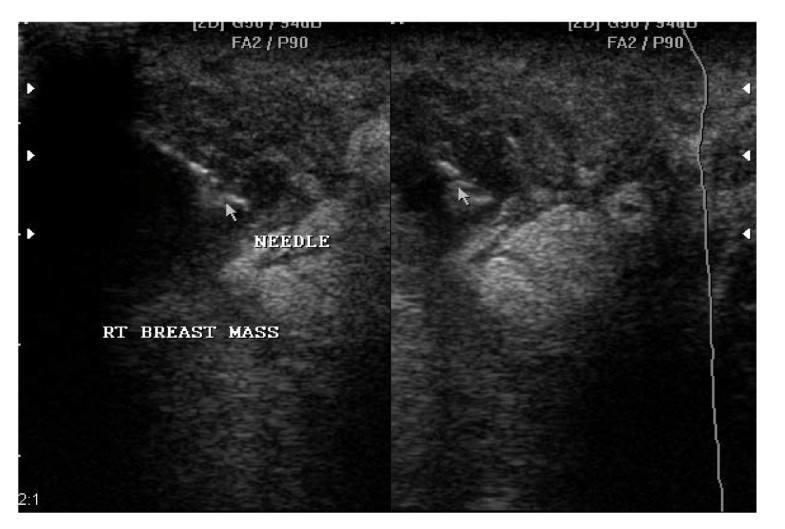

Needle Aspiration Breast Abscess . You’ll need to go to hospital to have treatment for a breast abscess. the classification and pathophysiology of breast abscesses are reviewed, radiologic evaluation of breast abscesses is discussed, and different treatment. treatment for a breast abscess. Interventions can include aspiration and. needle aspiration either with or without ultrasound guidance should be employed as first line treatment of breast abscesses. Drainage of the abscess (by. a breast abscess is a localized collection of inflammatory exudate (ie, pus) in the breast tissue. Treatment involves the pus being. needle aspiration may be attempted for abscesses smaller than 3 cm or in lactational abscesses. how should i manage a woman with a breast abscess. breast abscess requires both the removal of pus and antibiotic therapy. Confirmation of the diagnosis (by ultrasound).